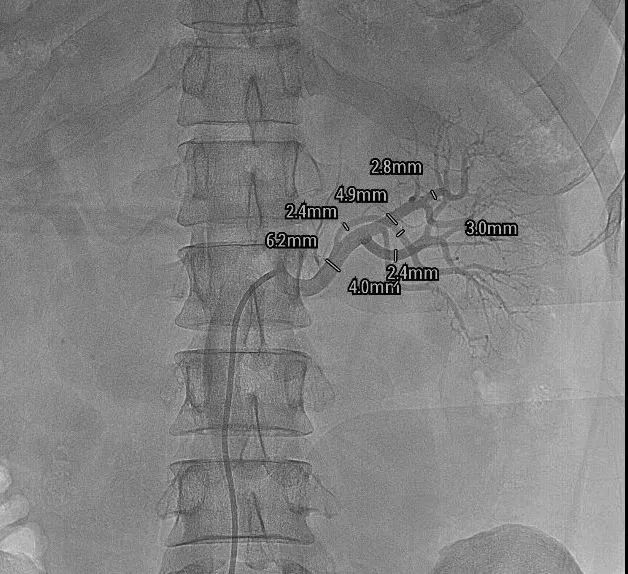

病友术前的肾动脉CTA提示右肾上有个错构瘤,术中肾动脉造影提示患者右肾动脉有4条一级分支,并且存在高位副肾动脉,这给手术增加了极大的难度。

医院积极联系了海南省人民医院王圣教授共同制定手术方案和现场手术指导,心血管介入团队与麻醉科、介入室密切配合,顺利将RDN消融导管送达迂曲的肾动脉分支部位,消融了患者双侧肾动脉主干及分支的77个位点。

选择血管